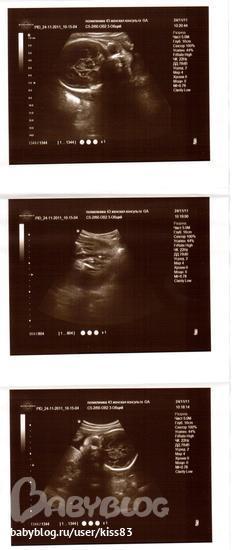

Но записана была к др врачу,а не к тому,что ходила в 12-14нед(добрая).Зато у этой(более строгая и ппротивная) в кабинете аппарат 3-4Д УЗИ.Порадовала меня показателями-все в норме,грит странно,почему плаценту в 21 нед на 3см посчитали низкой?что это норма.(Но я сравнила с результ снохи-мы на одном сроке с ней и в один день у одного и того ж доктора делали УЗИ)у нее 5 см было),так вот...сейчас у меня 4см.Но эт уже хорошо.Показала крупно писюльку)))Подтвердила что дееевочка)))Попросила ее фото сделать-прикиньте,150 р грит.Ну лан....отдала.Хотя на фото ну ниччче не понятно(((